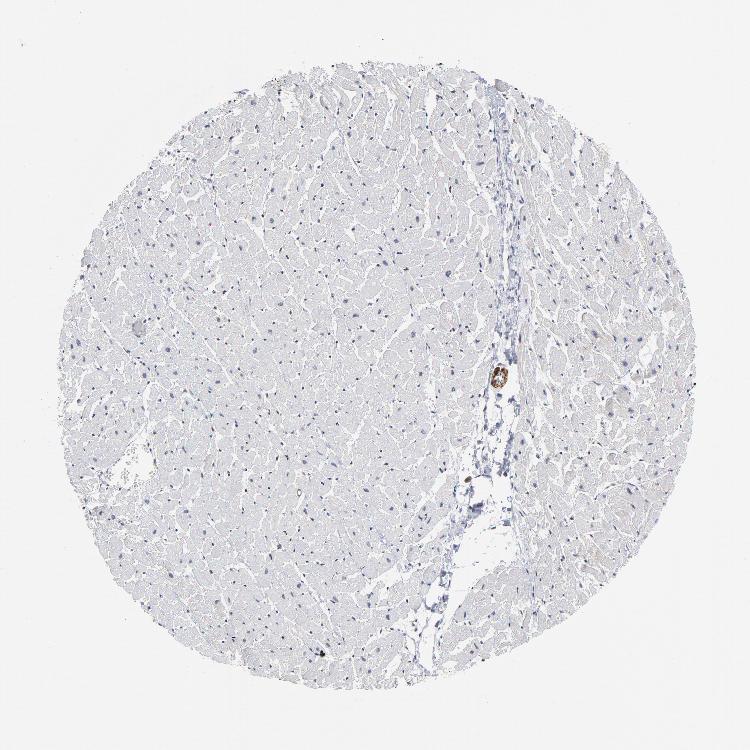

HEART MUSCLE - Antibody stainingi

Antibody staining in the annotated cell types in the current human tissue is reported as not detected, low, medium, or high, based on conventional immunohistochemistry profiling in selected tissues. This score is based on the combination of the staining intensity and fraction of stained cells.

Each image is clickable and will lead to virtual microscopy that enables deeper exploration of all samples and also displays staining intensity scores, fraction scores and subcellular localization as well as patient and tissue information for each sample.

Antibody HPA004122Antibody CAB062550Antibody CAB068181Antibody CAB068182

Cardiomyocytes HighLowHighHigh